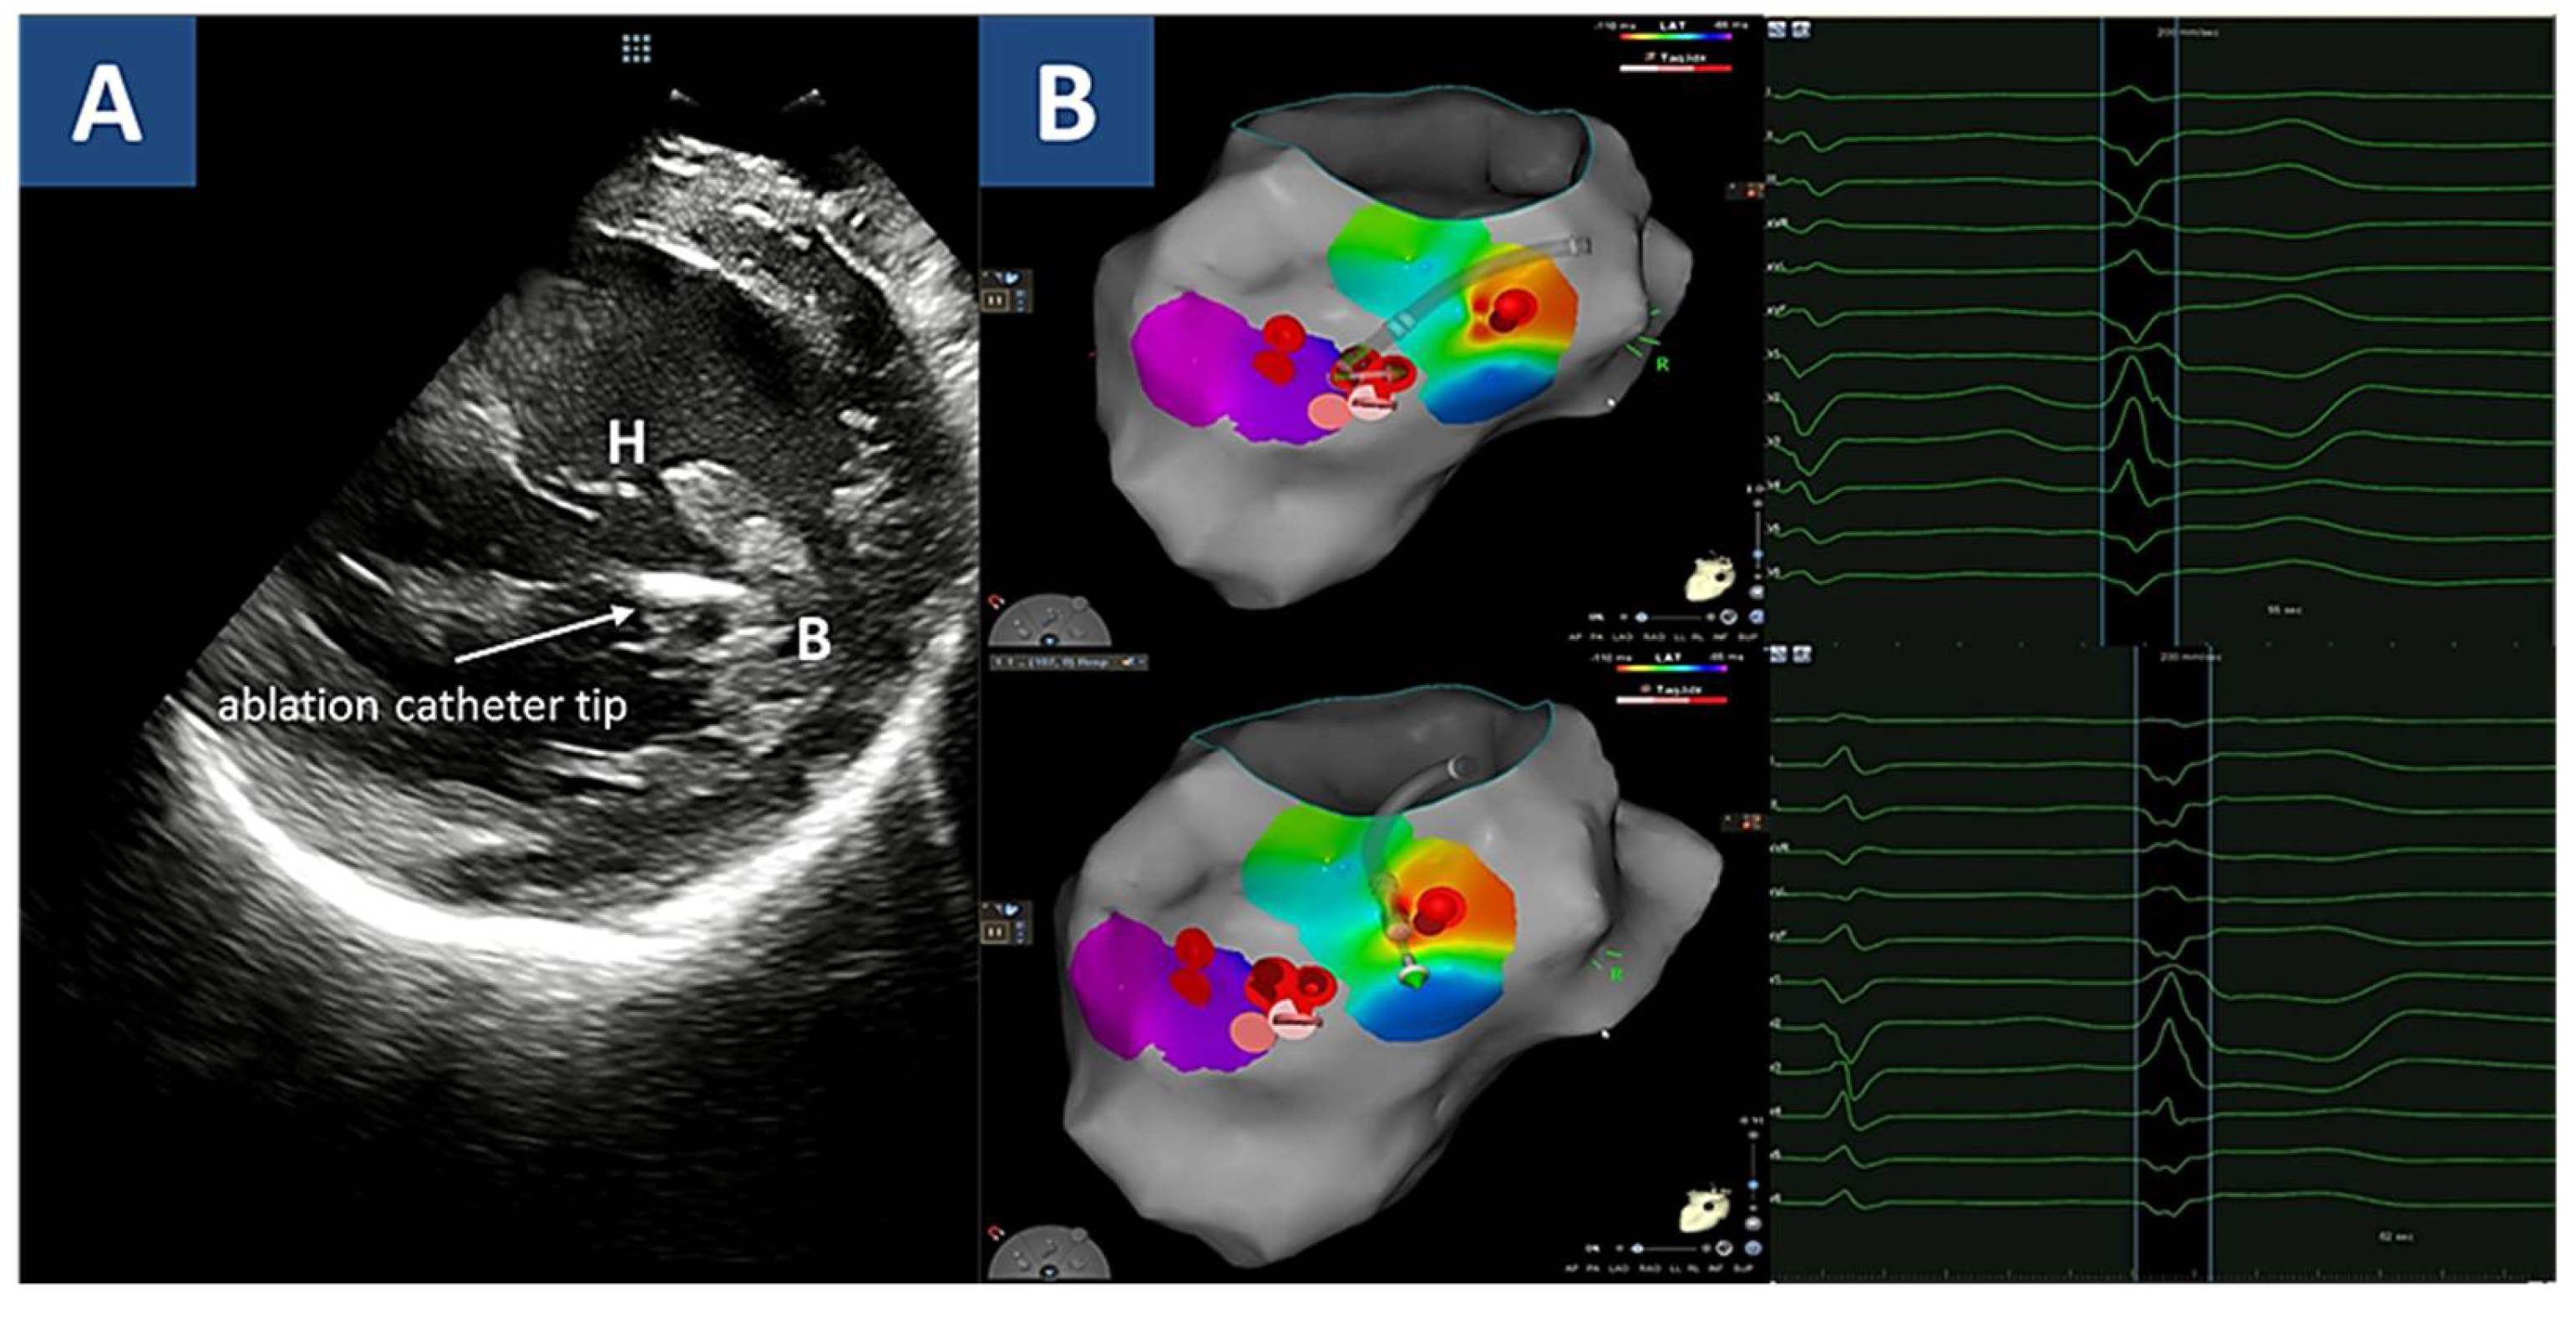

2. Case Report